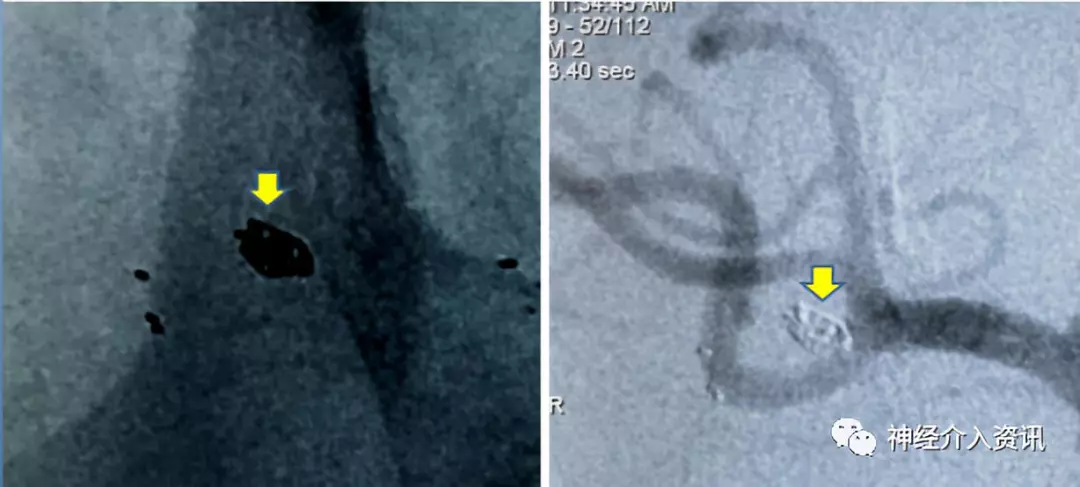

患者以“劳累后突发昏迷12小时”为主诉入院,入院查体颈强直,脑膜刺激征阳性,余神经系统查体无异常。头部CTA提示蛛网膜下腔出血,右侧大脑中动脉动脉瘤。完善术前准备后,于次日行全脑血管造影术,造影见右侧大脑中动脉动脉瘤,M1M2分叉处动脉瘤,2.8*2.5mm,瘤颈3.0mm;另一处脉络膜前动脉动脉瘤,1.5*1.0mm,瘤颈1.5mm。计划同时处理两处动脉瘤。

图二 多发动脉瘤